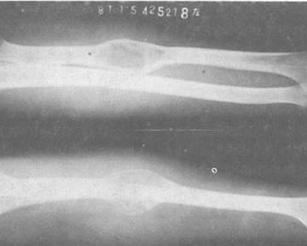

单房性骨囊肿(solitary bone cyst)囊内为一单腔,里面衬以薄膜并含草黄色液体,骨囊肿常位于肱骨和股骨上干骺端,年龄大的患者常位于髂骨,跟骨和掌跖骨,约2/3的病例无任何症状,1/3的病例局部有隐痛,酸痛,轻压痛,少数病人局部包块和骨增粗,绝大多数患者在发生或反复发生病理骨折而就诊,囊壁多因外伤甚至病理骨折后意外发现,除外伤外一般没有疼痛,股骨上端病变常因步态异常才引起注意。[1]